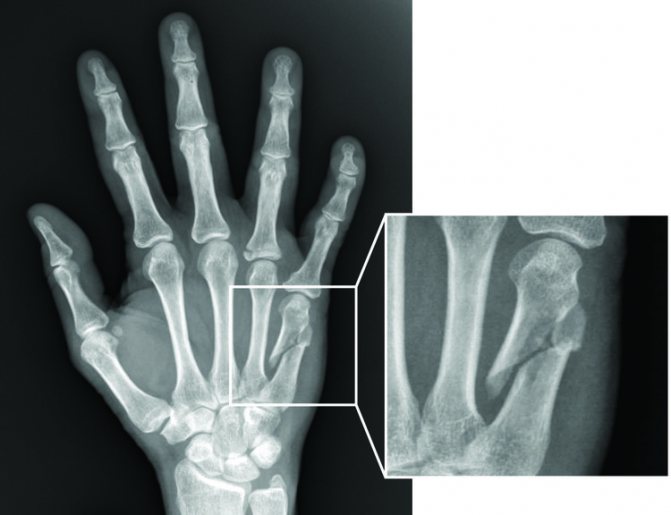

Конечным пунктом осмотра должно стать рентгеновское исследование. Именно на основании снимка ставится точный диагноз, определяется вид и сложность повреждений.

- рентгенографическое исследование – рентгенологические снимки делают в прямой и боковой проекциях, при необходимости – в косой. Снимок помогает выявить мелкие осколки, что важно для определения тактики лечения;